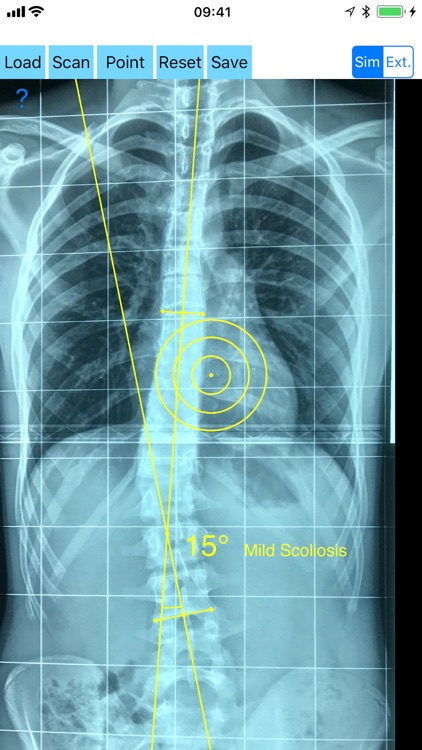

Cobb method is considered the standard for measuring curve size in scoliosis. Cobb angles are always measured from the superior end plate of the most cephalad end vertebra to the inferior end plate of the most caudal end vertebra in the curve. Meticulous line drawings and precise measurements is paramount importance in order to quantify the magnitude of spinal deformities and monitor the success or failure of treatment for scoliosis.

-Offers a very convenient way to determine the most accurate possibly way at once. By marking four points at the same X-ray, at each spine the App calculates the Cobb angle. In cases where values are out of normal ranges, the scoliosis is categorized according to measured angle as mild, moderate, severe. To simplify the process and to minimize inter-observer errors usually by not selecting the actual end vertebra, the app offers also in ext mode the ability to draw the vertical reference line through the patient’s sacrum and to identify more easily the end vertebrae s (ext method).